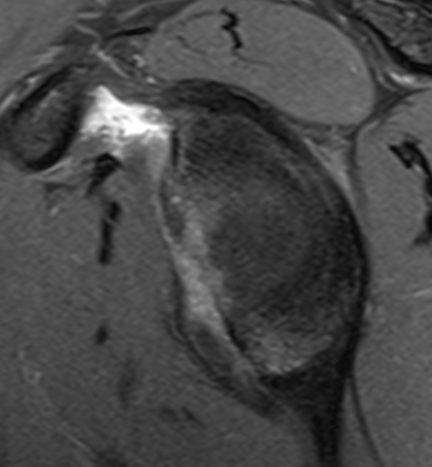

MRI

Anterior labral tears